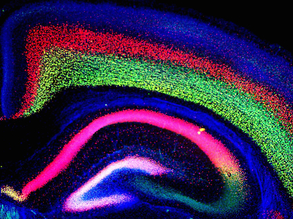

Complex Cortex